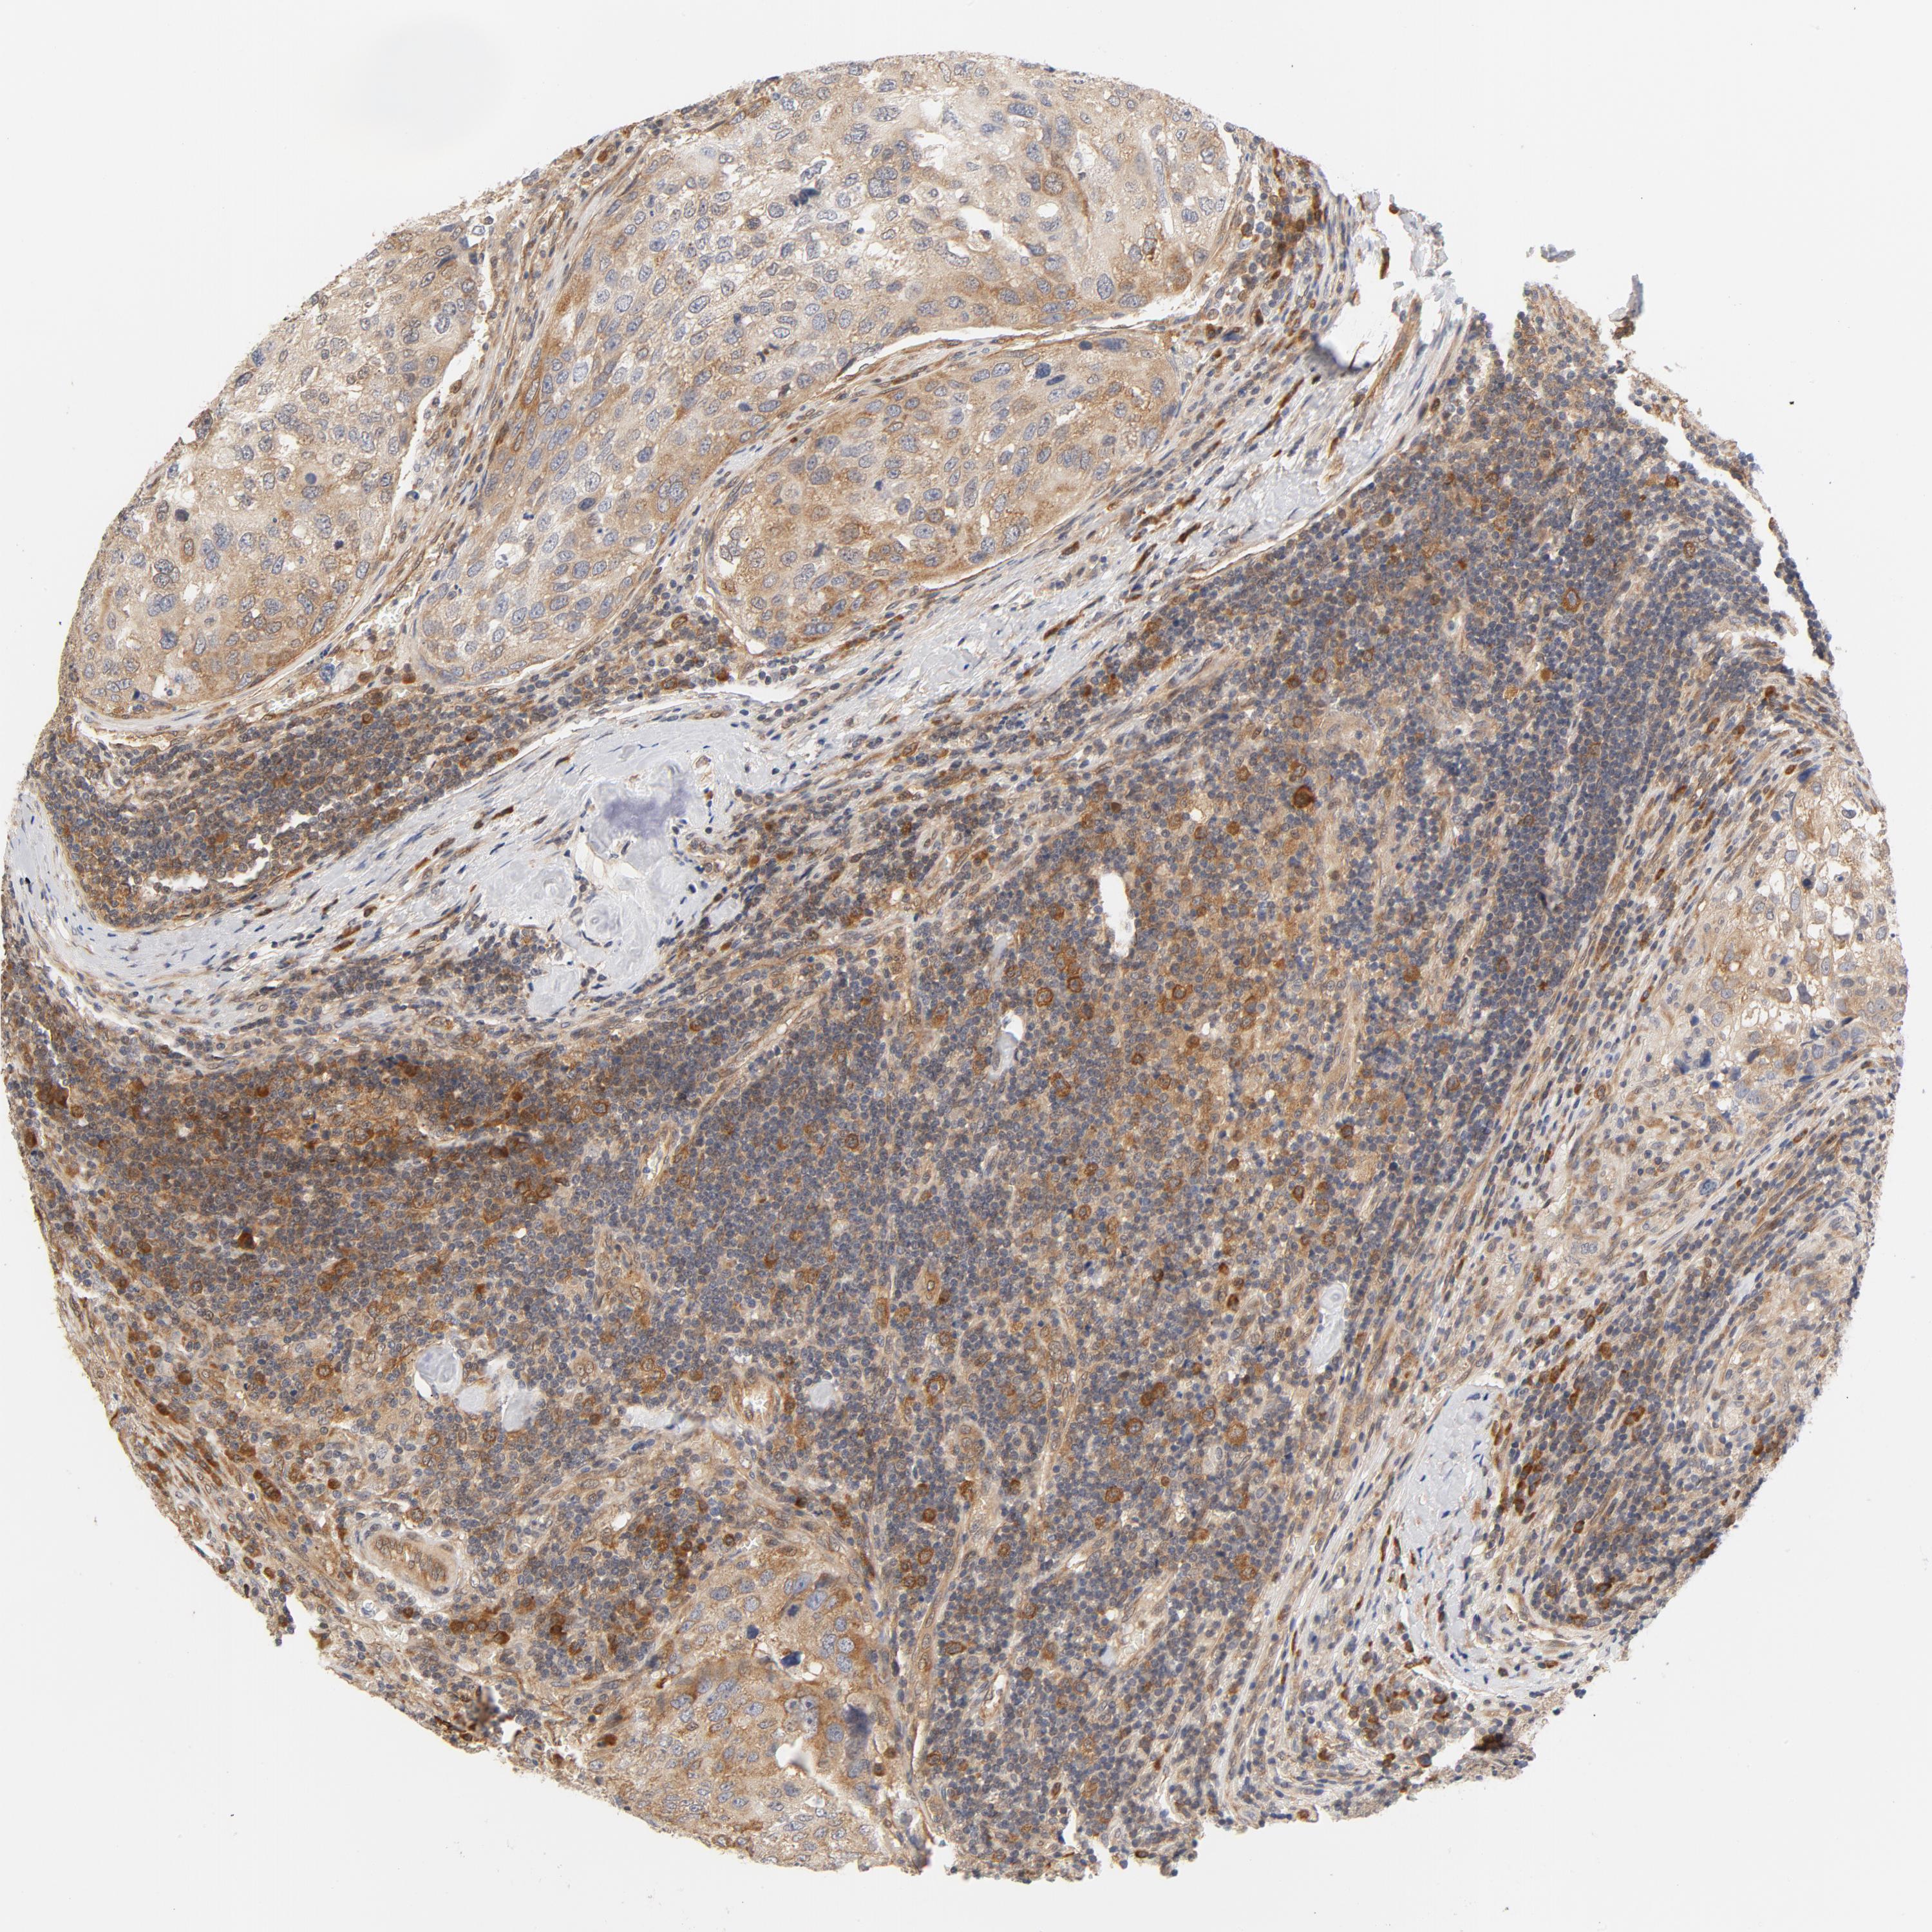

UROTHELIAL CANCER - Protein expressioni

A mouse-over function shows sample information and annotation data. Click on an image to view it in a full screen mode. Samples can be filtered based on level of antibody staining by selecting one or several of the following categories: high, medium, low and not detected. The assay and annotation is described here.

Antibody stainingi

Antibody staining in the annotated cell types in the current human tissue is reported as not detected, low, medium, or high, based on conventional immunohistochemistry profiling in selected tissues. This score is based on the combination of the staining intensity and fraction of stained cells.

Each image is clickable and will lead to virtual microscopy that enables deeper exploration of all samples and also displays staining intensity scores, fraction scores and subcellular localization as well as patient and tissue information for each sample.

Antibody CAB016316

Urothelial carcinoma, Low grade